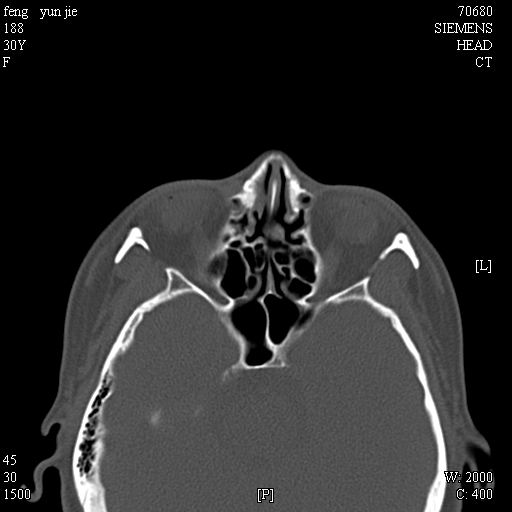

女,37岁,多年前鼻骨骨折过,现在穿刺有炎性分泌物

考虑:1、鼻骨陈旧性骨折;

2、额窦粘液囊肿(右侧水平额窦突入眶内上方)可能性大。

1)左侧鼻骨骨折(陈旧性)。2)双侧额窦及双侧筛窦炎症,伴右侧额筛窦黏液囊肿突入右侧眼眶。